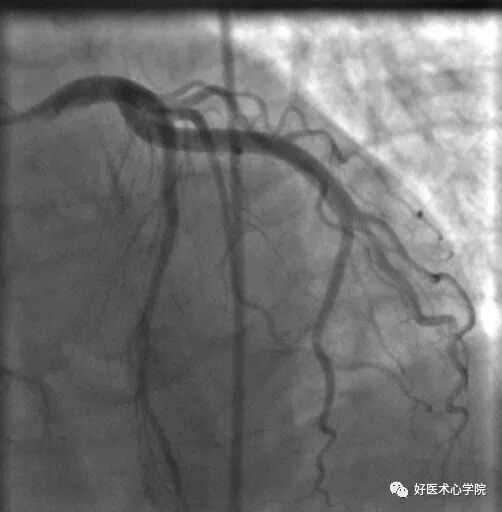

右前斜位:观察右冠近中段的体位。

• 右冠的右前斜位——右冠似字母 “L”